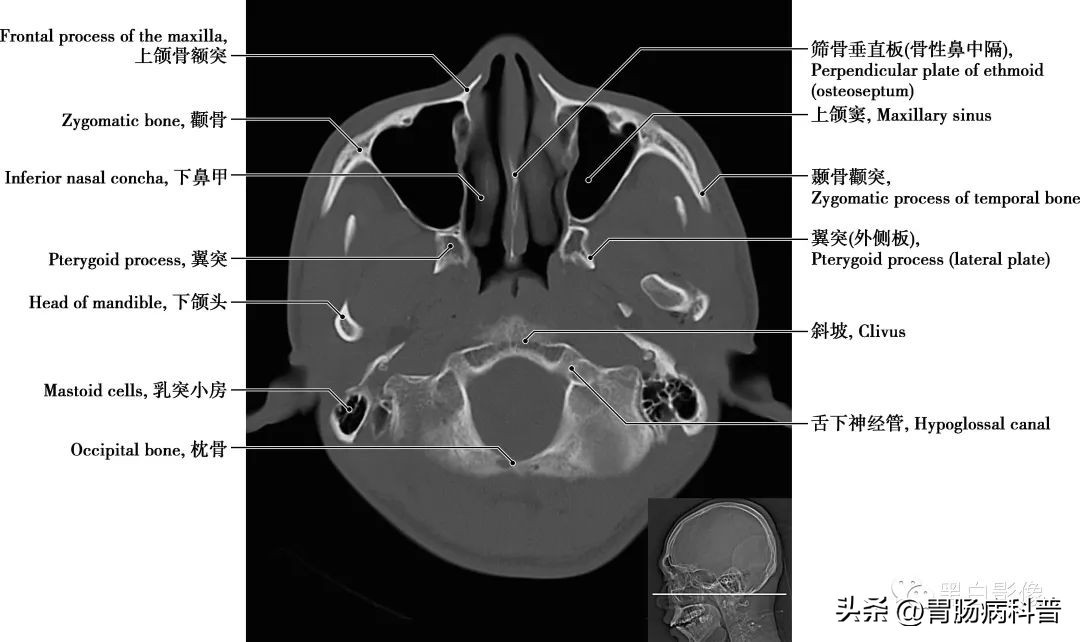

图1-2-19 经小脑扁桃体轴位切面

上颌窦 上颌骨体内的锥形空腔,位于上颌骨体内,窦壁为骨质,窦壁覆黏膜,向内侧开口于中鼻道,分为一底、一尖及前、后、上、下四个壁。由于窦口高于窦底部,故在直立位时若有炎性物不易自然流出。鼻泪管 为一膜性管道,上部包埋在骨性鼻泪管中,与骨膜紧密相结合;下部在鼻腔外侧壁黏膜深面,下部开口于下鼻道外侧壁的前部

图1-2-20 经枕骨大孔轴位切面

翼突 为蝶骨一部分,从蝶骨体与蝶骨大翼连接处下垂,向后敞开成为内侧板和外侧板,根部贯通一矢状方向的细管,称翼管,向前通入翼腭窝。下鼻甲 有两块,呈卷曲样,形成鼻腔外侧壁的一部分。起到空气进入肺以前的循环及过滤作用